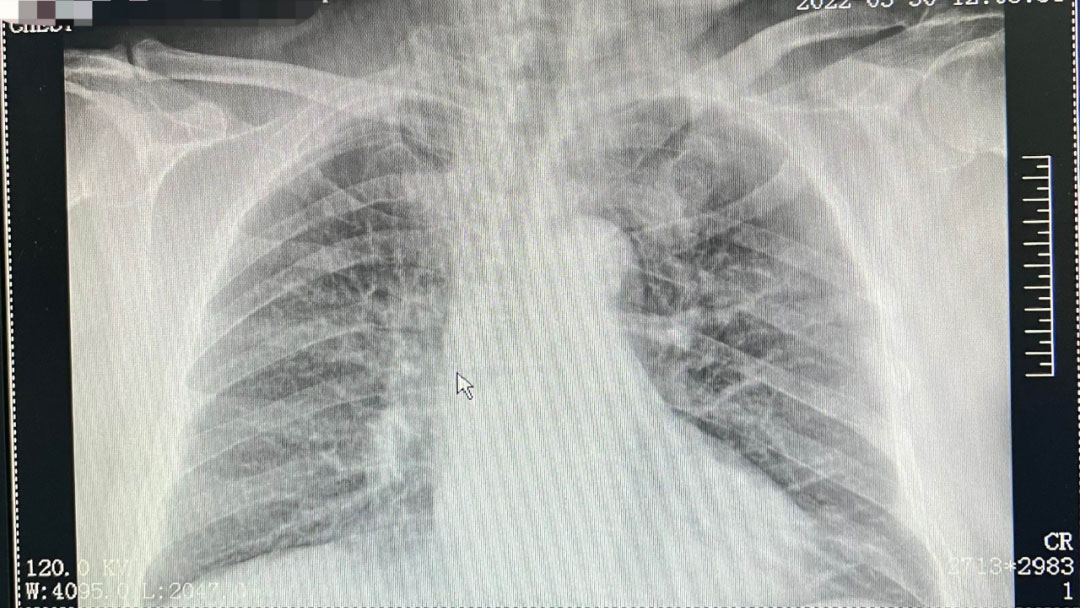

患者黄某某、和某某因病入住我院中外肿瘤科,经我院静脉治疗小组对患者进行充分评估及检查、与患者家属解释沟通后,中外肿瘤科静脉专科护士杜娟于3月30上午为患者行超声引导下PICC置管术,术中出血少,患者疼痛感轻,导管尖端位于上腔静脉。术后患者及家属对置管非常满意。